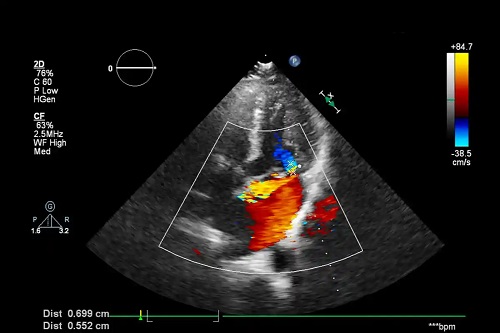

Este indicată efectuarea mai multor ecografii Doppler. Ele sunt aproape întotdeauna efectuate la fiecare 15 zile pentru a monitoriza evoluția. În plus, medicul poate prescrie ciorapi compresivi de tip 3.